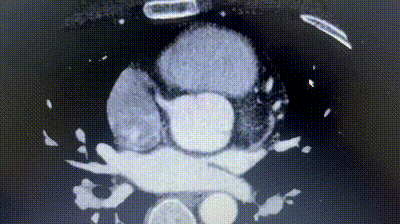

2. A ATC coronária revelou origem anômala da artéria circunflexa esquerda (CLX) a partir do seio coronariano direito, com curso entre a aorta e o átrio esquerdo.

3. A distância entre o ASD e o LCX aberrante era somente aproximadamente 6mm.